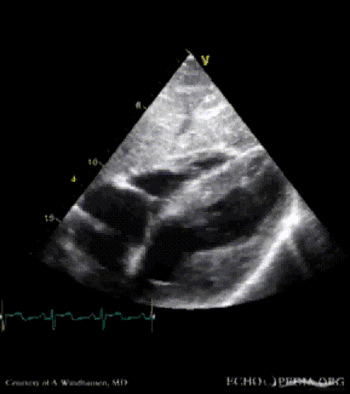

Severe Hypertrophic Cardiomyopathy (HCM)

Case description: Severe Hypertrophic Cardiomyopathy (HCM)

Courtesy of: A. Windhausen, AMC, The Netherlands

MM0003.gif MM0010.gif